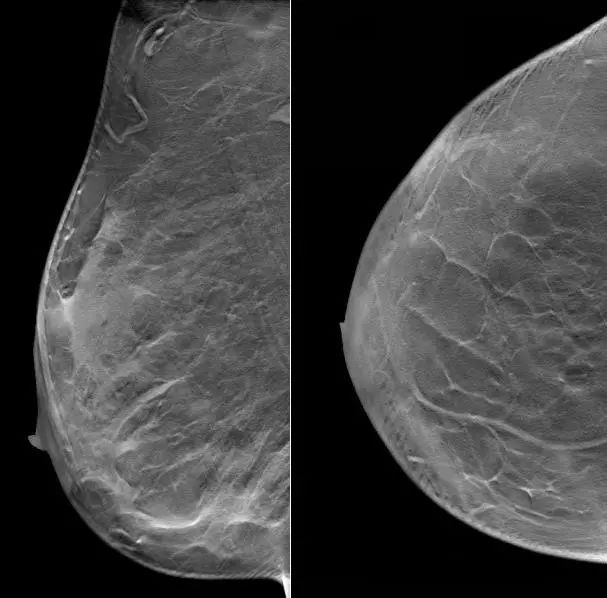

2021.7.6 钼靶示:右乳外上象限肿块,考虑乳腺癌(BI-RADS-5类)右腋下肿大淋巴结,M灶可能。

右乳外上象限不规则高密度肿块,边缘毛糙,大小约3.3×2.7cm,邻近皮肤牵拉增厚,右腋下见肿大淋巴结。

图2. 钼靶